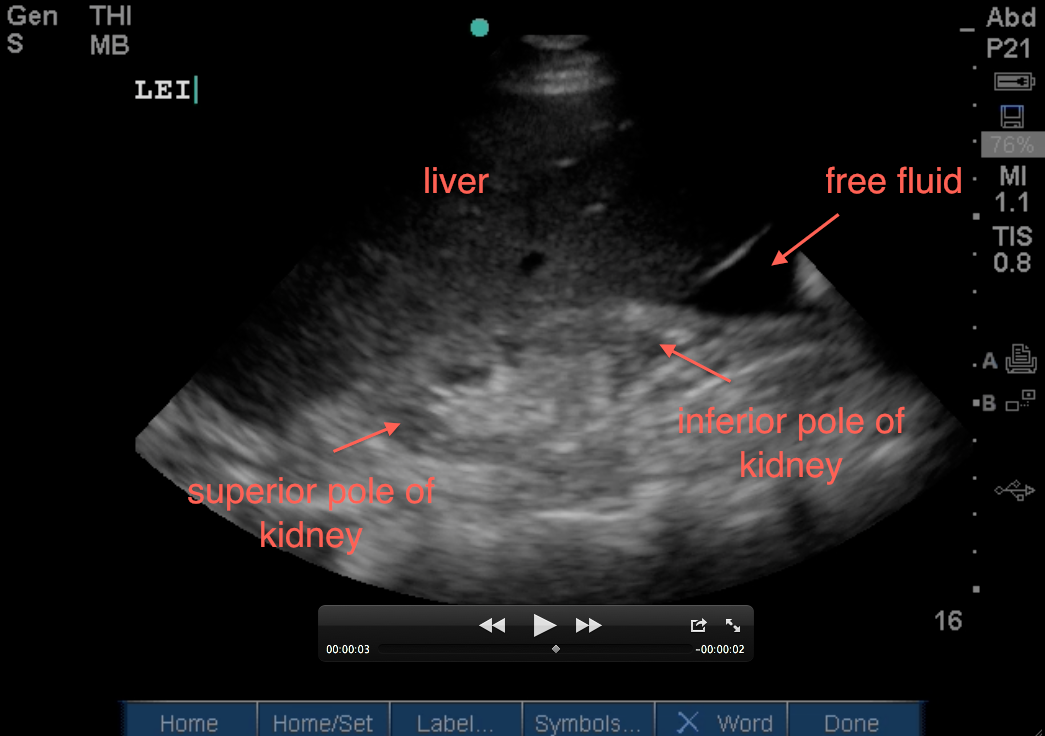

4. Evaluate between the left edge of the liver and the entire inferior pole of the kidney. This will also evaluate the right paracolic gutter. I was saving the best for last here. This image is key in not missing free intraperitoneal free fluid as this is where free fluid will be seen first in the right upper quadrant and with more accuracy than any other part of the right upper quadrant view.